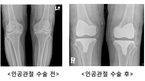

60세 이상 노년의 인구 80%가 겪고 있는 퇴행성관절염은 일평생 열심히 살아온 사람들의 숙명과도 같다. 쉬지 않고 움직이고 걷고 일해 온 탓에 무릎의 연골이 닳아버려 생기는 질환이기 때문이다. 관절염이 발전하면서 당연히 통증이 있었겠지만 치료를 미루고 미루다